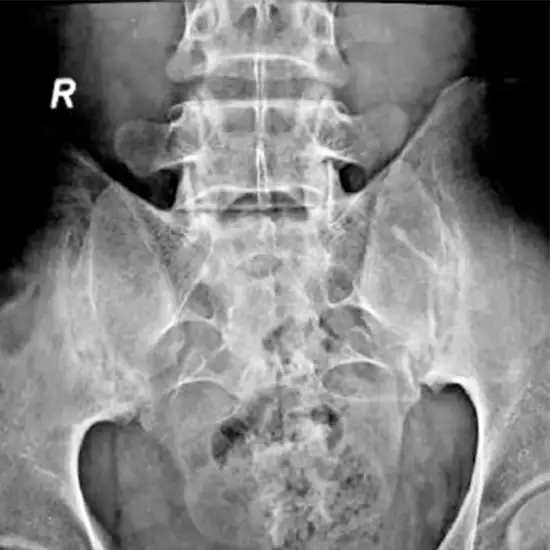

X-Ray The Sacro-Iliac Joints AP and Obl Views are used to visualize the area of the back where the spine meets the pelvis (hip bones).

The doctor prescribes this test to identify and diagnose the reason for lower back pain, which could be sacroiliitis (inflammation of this joint) or ankylosing spondylitis (a form of arthritis that affects the spine). In addition to detecting aberrant development or fracture of the bones in this region, the test can also monitor the bone's healing after it has been set.